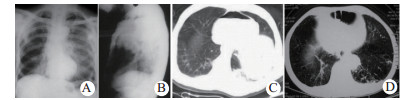

| 图 1 术前X线和CT诊断(A、B:例1张力性心包积气; C:例2血气心包; D:例3心包膈疝) Fig 1 Preoperative X-ray and CT diagnosis (A and B: case 1, tension pneumopericardium; C: case 2, hemopenumopericardium; D: case 3, pericardial diaphragmatic hernia) |